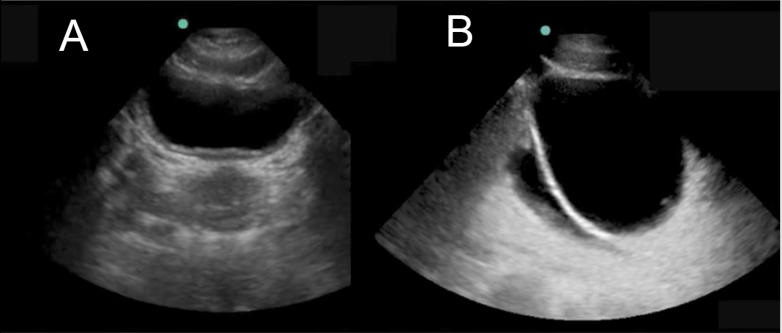

eFAST Pelvic View Image

A. No Fluid

B. With Fluid